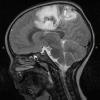

HSV-I Encephalitis (2)